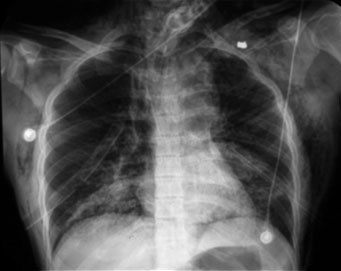

La radiografía de tórax, además de presentar evidencia de hemoneumotórax izquierdo y neumotórax derecho, mostró enfisema subcutáneo severo (figura 2), por lo que fue necesaria la colocación de sondas endopleurales bilaterales.

Asimismo, una radiografía tomada después de la colocación de sonda endopleural demostraría la imagen de apical izquierda y ensanchamiento mediastinal, lo cual sugirió lesión de aorta (figura 3).